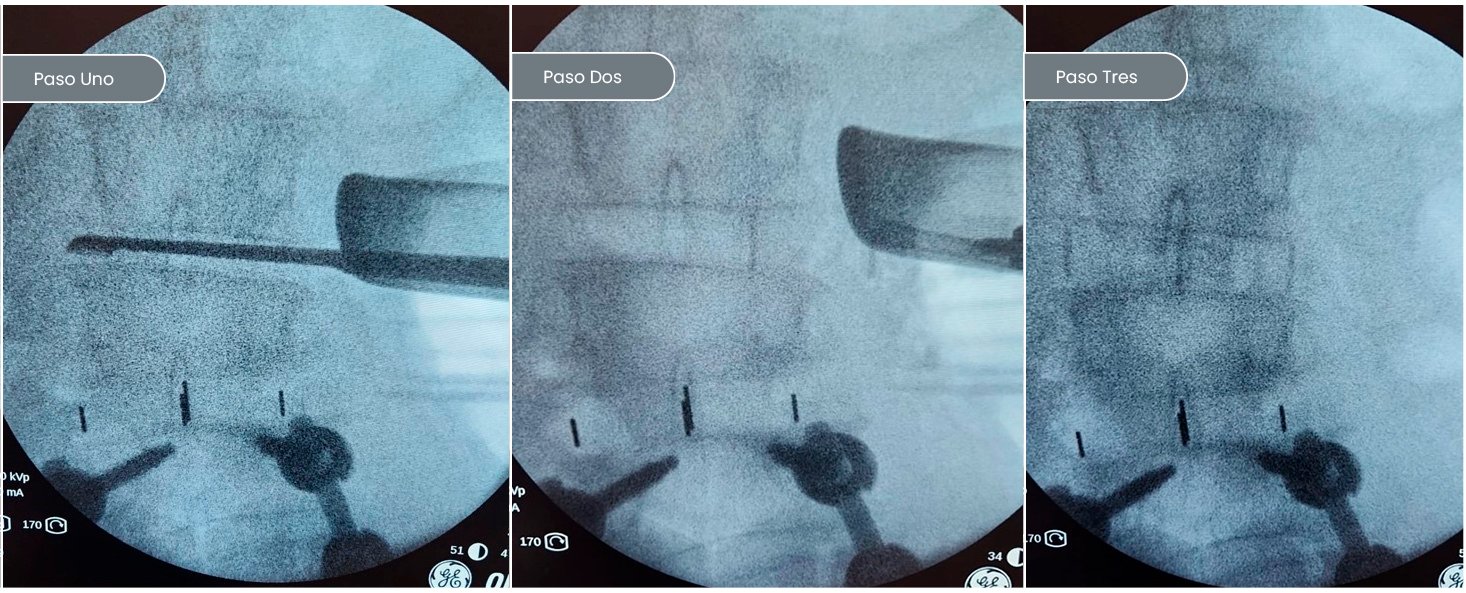

CHEQUEADO TODO EN ORDEN, SE POSICIONA BOCA ABAJO Y COMENZAMOS EL SEGUNDO ABORDAJE A LA COLUMNA PARA CORRECCIÓN Y ESTABILIZACIÓN DEFINITIVA

6 MESES DESPUÉS

ESCOLIOSIS IDIOPÁTICA

Siempre que se agotan o no resultan las opciones terapéuticas conservadoras (utilización de corsés o terapias físicas) y las curvas continúan aumentando su angulación. La cirugía de corrección es la opción correcta, se caracteriza por abordar por la espalda la curvatura escoliótica y colocar una serie de tornillos pediculares en cada una de ellas. Una vez colocados y bajo control radioscópico de guía y en conjunto con un médico neurólogo para monitorizar el funcionamiento de la médula espinal. Unimos, a través de dos barras conectoras cada uno de los tornillos. Se efectúan las maniobras de corrección de las curvas. Como bien sabemos, los patrones de curva cambian de paciente a pacientes. Es por eso que la indicación de instrumentación, más las maniobras de corrección varían de paciente a paciente. El espíritu de nuestro equipo es siempre el de restringir el número de vértebras instrumentadas para dar capacidad a las vértebras que están libres para ayudar a compensar el eje espinal y obtener un resultado óptimo.